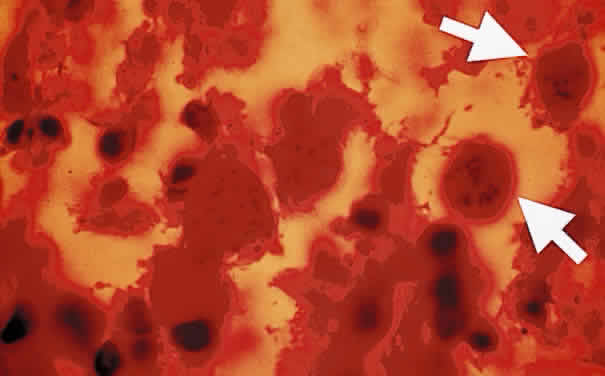

Sporozoites are found in the oocyst. Each sporozoite measures 10 to 12 μm in diameter. The sporozoite is produced in the intestines during the enteroepithelial part of the Toxoplasma life cycle. Toxoplasma organisms divide by endodyogeny (asexual reproduction), schizogony (splitting of nuclear material), and sexual reproduction involving the gametocytes. The gametocytes are found throughout the small intestines, especially in the ileum of the definitive host. The male gametocytes produce microgametes, which have the ability to fertilize macrogametes. After fertilization of the macrogamete, the zygote becomes surrounded by an oocyst wall and is shed in the feces of infected cats. Sporogony, which spans approximately 3 to 21 days, occurs within the oocyst outside of the host.1 The sporulated oocysts become infectious. Millions of oocysts may be excreted in the feces of an infected cat. Under conditions of moist and warm soil, the oocyst may remain infectious for more than a year.2 The oocyst appears to be an important method for the transmission of toxoplasmosis. Once ingested, the oocyst wall is digested by the gastric enzymes, trypsin and pepsin, thereby liberating Toxoplasma sporozoites. Shedding of the oocyst begins 1 to 24 days after the ingestion of the parasite by the cat. Sporulation requires 2 to 3 days at 24°C and 14 to 21 days at 11°C and does not occur above 37°C. Dry heat and exposure to temperatures above 66°C render the oocyst noninfectious. Puppies are susceptible to infection with Toxoplasma organisms and tend to shed more oocysts than adult cats.3 The reinfection of cats by Toxoplasma rarely leads to excretion of oocyst.